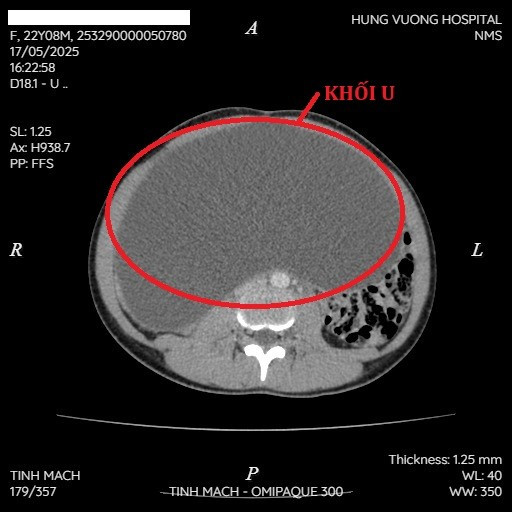

Khối u buồng trứng khổng lồ trên phim chụp - Ảnh BVCC